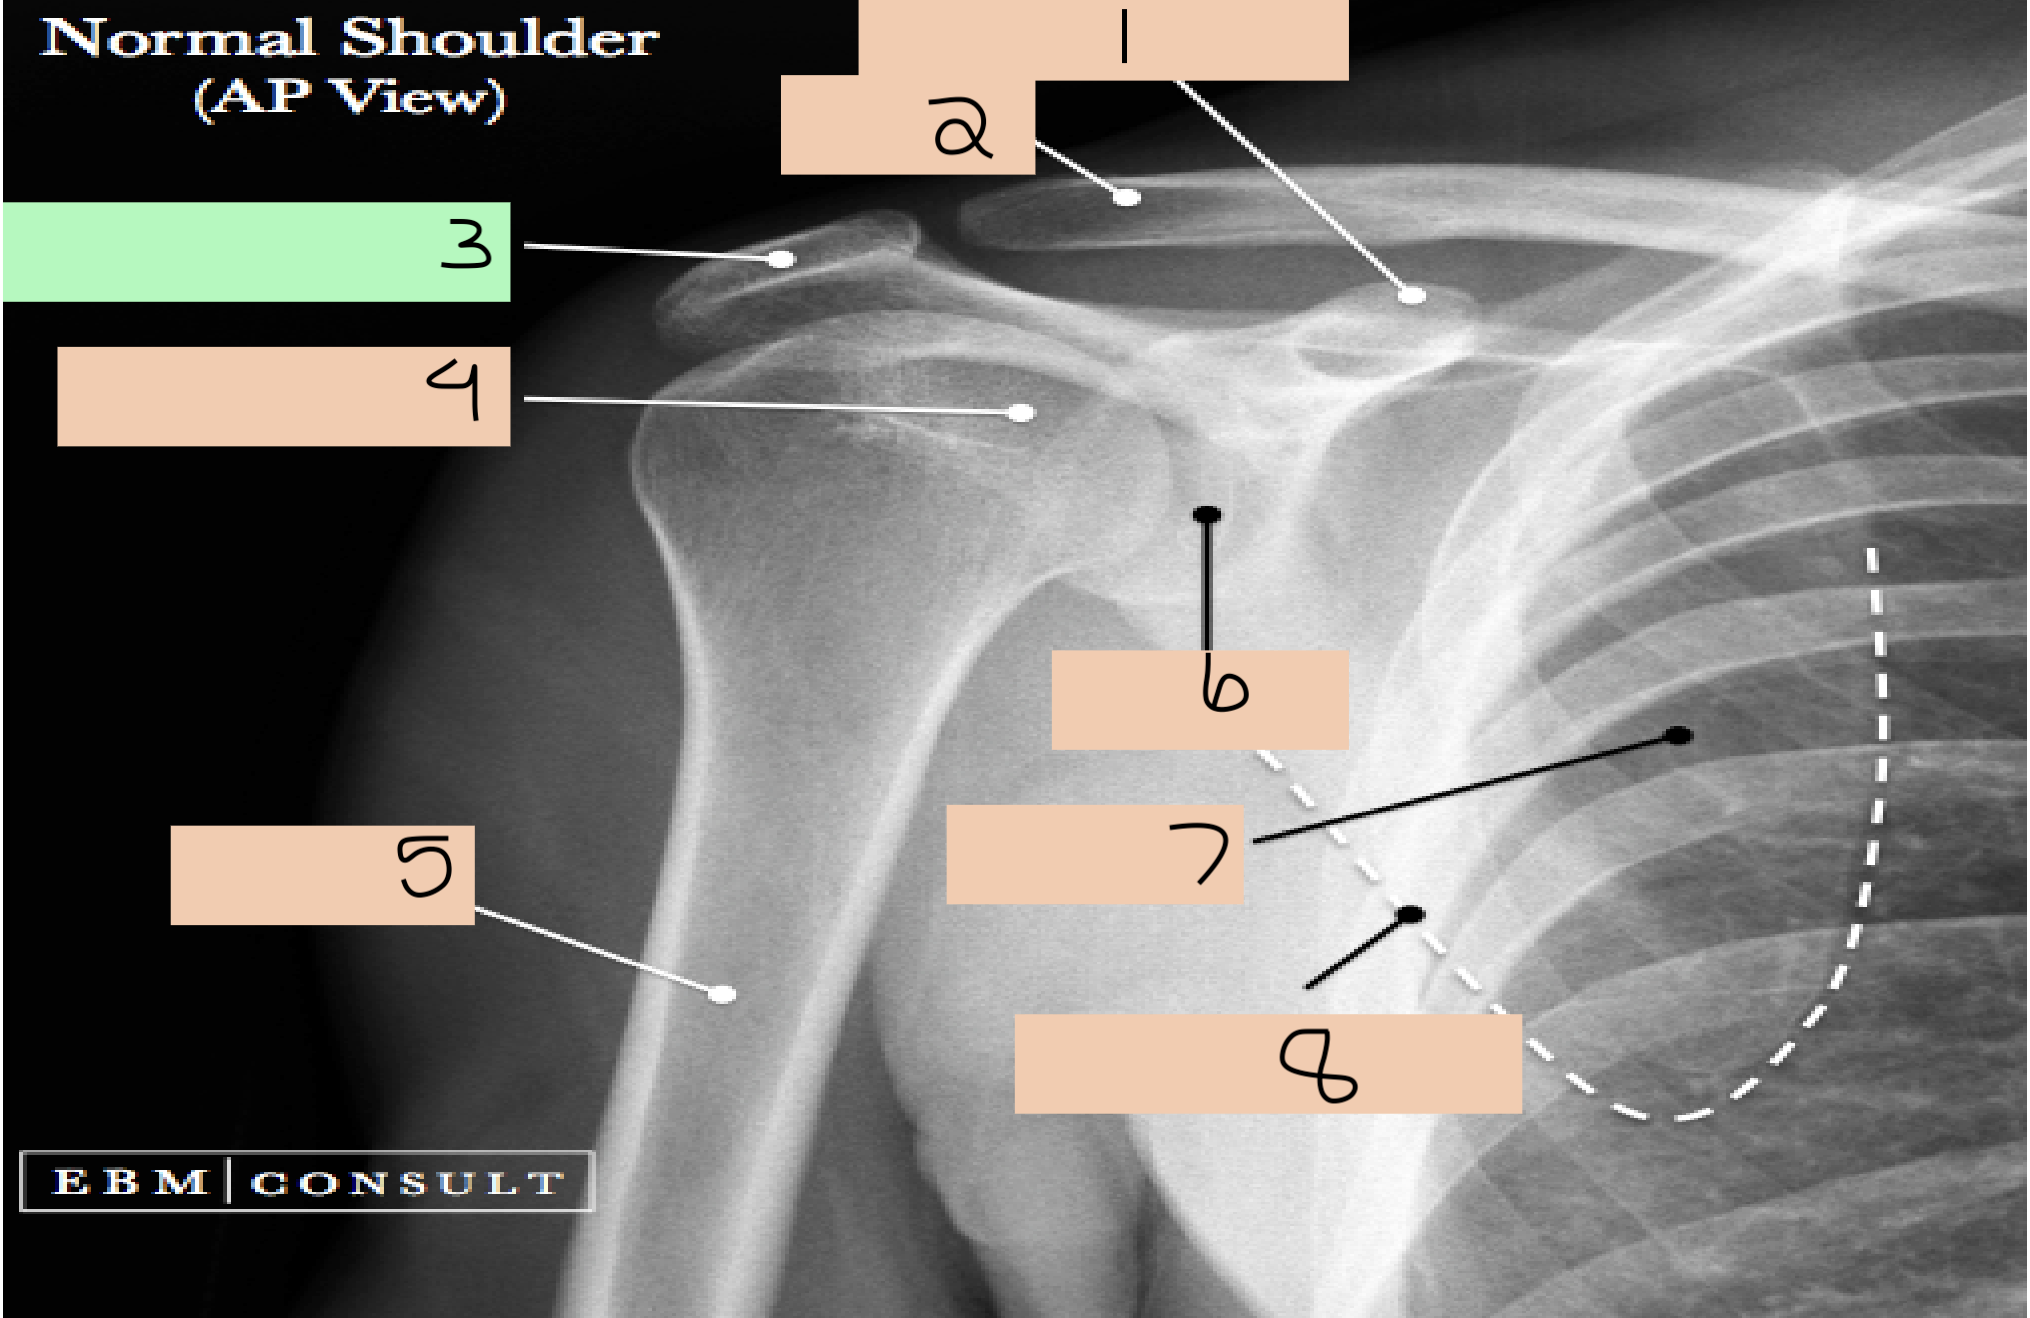

1

1st rib

2

clavicle

3

sternoclavicular joint

4

medial border scapula

5

inferior angle scapula

6

superior angle scapula

7

superior border scapula

8

coracoid process

9

glenoid fossa

10

lateral border scapula

12

acromioclavicular joint

13

acromion process

14

head of humerus

15

anatomical neck

16

greater tubercle

17

intertubercular groove

18

lesser tubercle

19

surgical neck